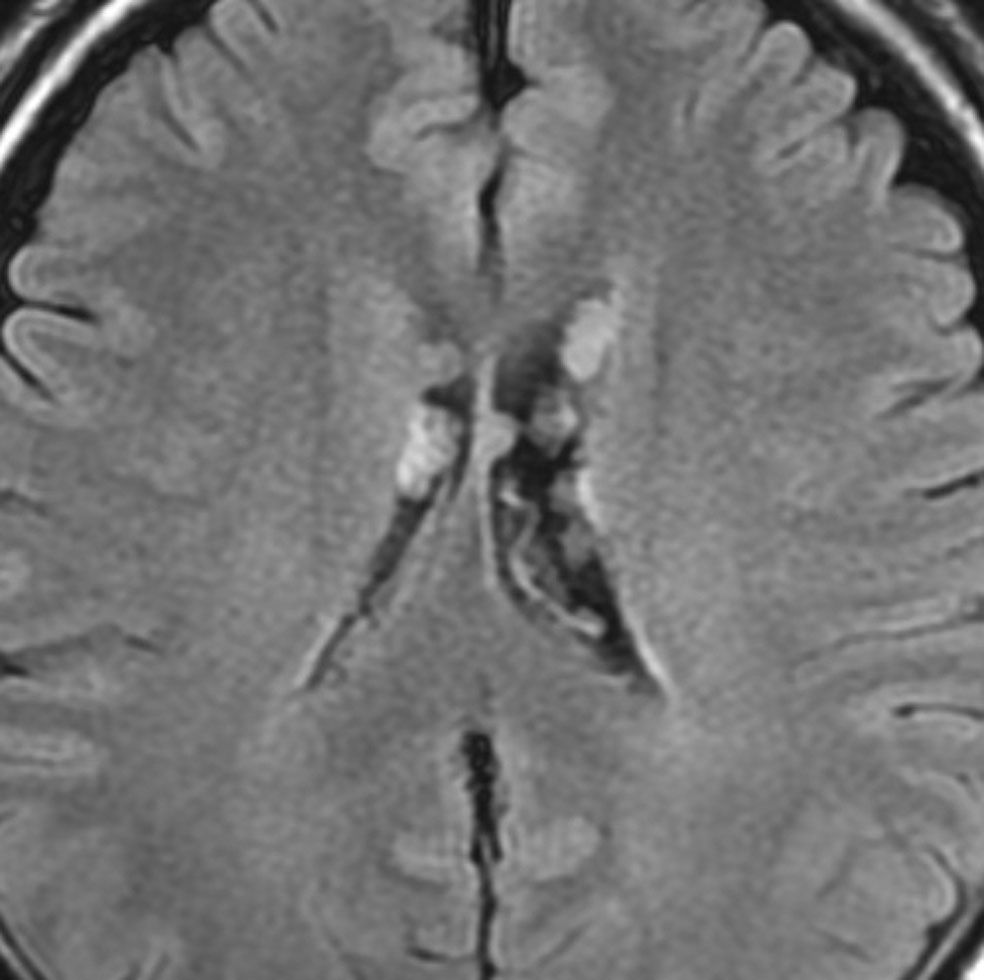

無症状で偶然発見された47歳女性の側脳室内上衣下腫

無症候で偶然発見された左側脳室前角尾状核頭に接したsubependymoma。定位脳生検で病理診断を得たましたが,3年間の観察で徐々に増大しました。左上が発見時,1年後(右上),2年後(左下),3年後(右下)

CTではやや低吸収,T1ガドリニウムでは低信号となりガドリニウム増強されません。小さな上衣下腫の場合は等吸収あるいは等信号のものも多いです。小さく点状に造影されている部分があるがこれは定位脳手術痕(track)です。

左中前頭回からの経皮室法 left middle frontal gyrus transcortical approach で全摘出できました(右図)。